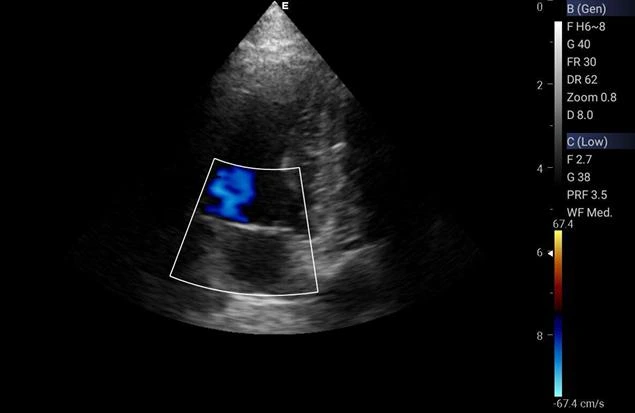

A ecocardiografia é um exame não invasivo e indolor que permite avaliar o funcionamento do coração dos animais.

O exame de ecocardiografia é feito por meio de ultrassom, que permite visualizar em tempo real as estruturas do coração do animal.